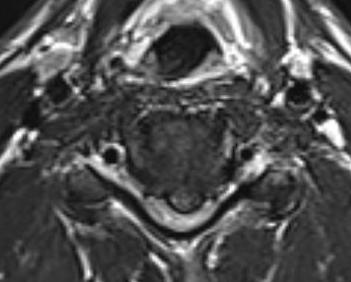

Paracentral disc

Foraminal disc

- in contrast to lumbar spine both posterolateral and central HNP compress exiting nerve root

C. Intraforaminal - most common / often dermatomal distribution